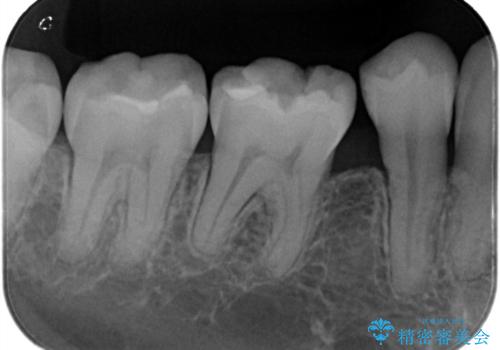

左下7番咬合面にコンポジットレジン修復されてり、経年劣化による着色や歯質との境目にう蝕を認め、セラミックインレーでのやり替えとなりました。

左下7番咬合面にコンポジットレジン修復されてり、経年劣化による着色や歯質との境目にう蝕を認めました。

コンポジットレジンとセラミックの物性的特徴を説明し、セラミックインレーでのやり替えとなりました。